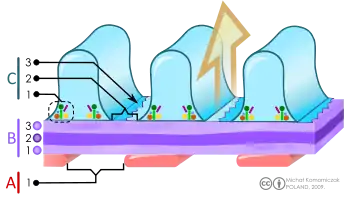

B. Glomerular basement membrane: 1. lamina rara interna 2. lamina densa 3. lamina rara externa

C. Podocytes: 1. enzymatic and structural proteins 2. filtration slit 3. diaphragm

The renal corpuscle is the site of the filtration of blood plasma. The renal corpuscle consists of the glomerulus, and the glomerular capsule or Bowman's capsule.[3]: 1027

The Bowman's capsule, also called the glomerular capsule, surrounds the glomerulus. It is composed of a visceral inner layer formed by specialized cells called podocytes, and a parietal outer layer composed of simple squamous epithelium. Fluids from blood in the glomerulus are ultrafiltered through several layers, resulting in what is known as the filtrate.